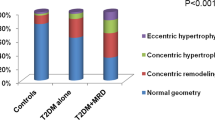

Detailed echocardiographic evaluation was done using standard views including parasternal long axis and short axis view at three levels of the left ventricle and apical 4-, 3- and 2-chamber views. All echocardiographic studies were performed on the GE VIVID S60 2D echocardiographic system (GE healthcare, US) with 1.3–4.5 MHz 3Sc-RS adult probe. Echocardiographic images were stored for offline analysis. Left ventricular (LV) internal diameter during end diastole (LVEDD), LV internal diameter during end-systole (LVESD), wall thickness of posterior wall of LV (PWT), and interventricular septum (IVST) were recorded. Left ventricle ejection fraction measurements were taken by using M-Mode and Modified Simpson’s method. LV end diastolic volume (LVEDV) and LV end systolic volume (LVESV) were measured by tracing the border between myocardium and LV cavity as recommended in the 2015 American Society of Echocardiography/European Association of Cardiovascular Imaging (ASE/EACVI) guidelines [10]. LV mass (LVM) and LV mass index (LVMI) were calculated using Devereaux formula [11]. LV hypertrophy (LVH) was deemed to be present when LVMI was more than 95 g/m2 in women and 115 g/m2 in men.

Echocardiographic findings

The main findings on traditional echocardiography are shown in Table 2. LV dimensions, including LV end-systolic and end-diastolic diameters, LV mass, LV mass index (LVMI), inter-ventricular septum (IVS) thickness and posterior wall thickness were similar in both groups. LV ejection fraction (LVEF), peak early diastolic transmitral velocity (E), peak late diastolic transmitral velocity (A) and E/A ratios were also similar in both groups. There was a significant difference in early diastolic mitral annular velocity at interventricular septum (septal e’) (7.1 ± 2.5 vs. 8.2 ± 2.8; p = 0.031) and lateral wall (lateral e’) (9.2 ± 2.9 vs. 10.4 ± 3.8; p = 0.045) measured by tissue doppler imaging in the DKD and NDKD groups. The E/e’ ratio was significantly higher in DKD (11.9 ± 4.4 vs. 9.8 ± 3.5; p = 0.004) and so was the mitral E wave deceleration time (in milliseconds) (209.2 ± 41.5 vs. 189.1 ± 48.0; p = 0.017), compared to those with NDKD. Overall, abnormal E/e’ (> 12) was seen in 40 (34.2%) patients. Higher proportion of patients with DKD had abnormal E/e’ compared to those with NDKD (44.6% vs 24.6%; p = 0.022).

We studied echocardiographic parameters of patients with CKD stages 3–5 and normal ejection fraction and found that the ratio of peak early diastolic transmitral velocity to early diastolic mitral annular velocity (E/e’) was abnormal in nearly a third of patients. Further, E/e’ was higher in patients with DKD, compared to those with NDKD (11.9 ± 4.4 vs. 9.8 ± 3.5; p = 0.004). E/e’ ratio is an estimate of LV end diastolic pressure and is widely considered to be a non-invasive marker of LV diastolic dysfunction [15]. We also found that both septal e’ (7.1 ± 0.25 vs. 8.2 ± 2.8; p = 0.031) and lateral e’ (9.2 ± 2.9 vs. 10.4 ± 3.8; p = 0.045) were significantly lower in the DKD group, in addition to higher mitral E wave deceleration times (209.2 ± 41.5 vs. 189.1 ± 48.0; p = 0.017). While the lower septal and lateral e’ values indicate impairment in LV relaxation and early diastolic recoil, longer DT indicates LV stiffness-these are the key underlying mechanisms for diastolic dysfunction [16]. Despite the fact that both groups had similar LVMI and systolic function, the observed differences in the indices of LV diastolic function suggest that there are additional mechanisms at play in patients with DKD compared to those with other etiologies for CKD. In a study similar to ours, Miyazato et al. reported that echocardiographic parameters of LV diastolic function were more impaired in those with diabetic nephropathy, compared to those with chronic glomerulonephritis [17]. There too the authors observed no difference in LV structure and systolic function between the two groups. Another study by Han et al. too found higher E/e’ ratios in patients with DKD compared to those with NDKD [18]. It has been described that the diabetic state is associated with increased oxidative stress, elevated levels of pro-fibrotic and pro-inflammatory cytokines and accumulation of advanced glycation end products [19]. These abnormalities can lead to myocyte apoptosis, fibrosis, and LVH resulting in a condition referred to as diabetic cardiomyopathy-an entity that is still poorly understood [20,21,22]. This condition manifests as diastolic dysfunction in the presence of preserved EF in the initial stages, with systolic dysfunction developing over time. Some of these factors like LVH and fibrosis are also operative in non-diabetic CKD [3, 23]. However, in addition, diabetic state is also associated with abnormal myocyte relaxation due to abnormal calcium handling in cardiomyocytes [24]. Prognostically, the presence of diastolic dysfunction assumes importance since evidence suggests that it is associated with higher all-cause and cardiovascular mortality [25]. Even in our study, patients with DKD had poorer cardiovascular outcomes in a relatively short follow-up period. These findings make a strong argument for the routine assessment of diastolic function in patients with DKD.

A low GLS (> − 16%) suggestive of LV systolic dysfunction was seen in approximately 30% of our study population even though the study included only those with a normal LVEF. This confirms the findings of previous studies that strain imaging-derived GLS precedes changes in EF observed by conventional echocardiography [29,30,31]. GLS has been shown to be a predictor of all-cause and cardiovascular mortality in several studies [7, 32, 33]. However, there was no difference in GLS between the DKD and NDKD groups in our study. This indicates that, although deformation imaging is able to identify the so-called “subclinical LV systolic dysfunction” in almost a third of these patients, DKD does not seem to be associated with a worse systolic function compared to those with NDKD in our study. Further, we found that patients with a low GLS (> − 16%) had higher E/e’ compared to those with normal GLS (12.6 ± 5.1 vs. 10.0 ± 3.3; p = 0.002). Although conventional wisdom is that GLS is a marker of subclinical LV systolic dysfunction, recent studies have suggested that it may provide additional information. A study by DeVore et al., showed that GLS may be a marker of myocardial fibrosis and hence diastolic dysfunction by showing an association between abnormal GLS and higher levels of biomarkers of collagen synthesis and NT-proBNP in blood [34]. The finding in our study that those with abnormal GLS had higher E/e’ (indicating diastolic dysfunction) suggests myocardial fibrosis as a possible explanation for impaired diastolic function. However, it remains unclear as to why DKD group had higher E/e’ compared to NDKD group even though both groups had similar proportion of patients with impaired GLS. It is possible that apart from myocardial fibrosis, there are additional factors such as abnormal myocardial relaxation (as described above) that account for higher E/e’ in the DKD group.